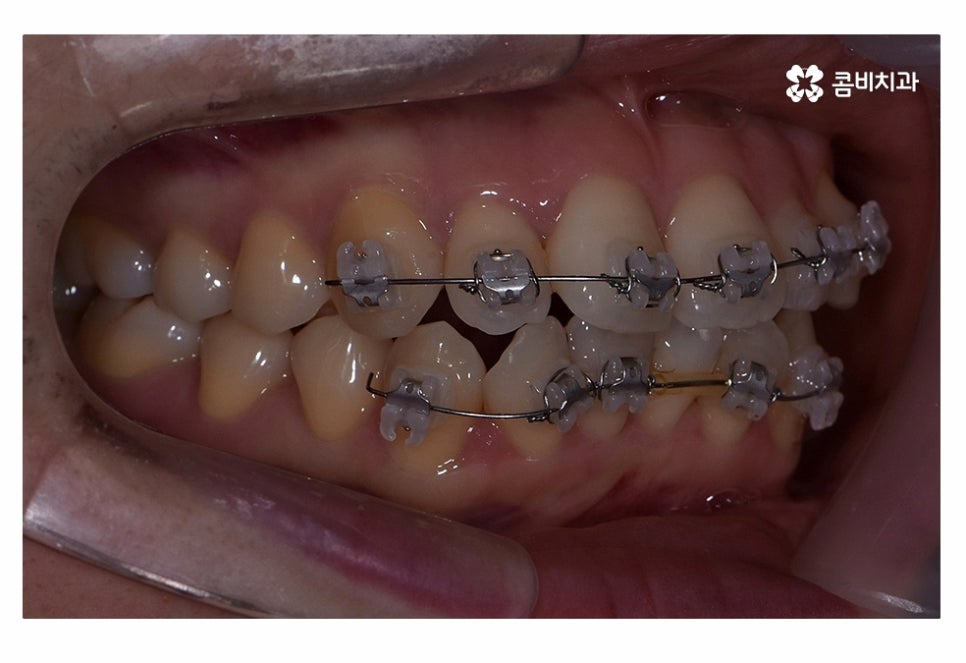

오늘은 치아부분교정 사례와 함께 부분교정에 대한 설명을

해드릴 예정이며 위 사진에서 보시는 환자분의 경우

정면에서 보는 치열과 측면의 차이가 다소 크다는 것을 알 수 있는데요.

이처럼 치열은 정면에서 보이는 것만이 아닌 얼굴형과 골격을

고려하여 치료 계획을 세워야 한다는 것을 알 수 있어요.

교합이 정상적이고 치아의 이동 공간을 고려할 때

치아부분교정이 가능했던 환자분이었기 때문에 윗니와 아랫니에

각각 부분교정이 진행된 사례라고 할 수 있는데요.